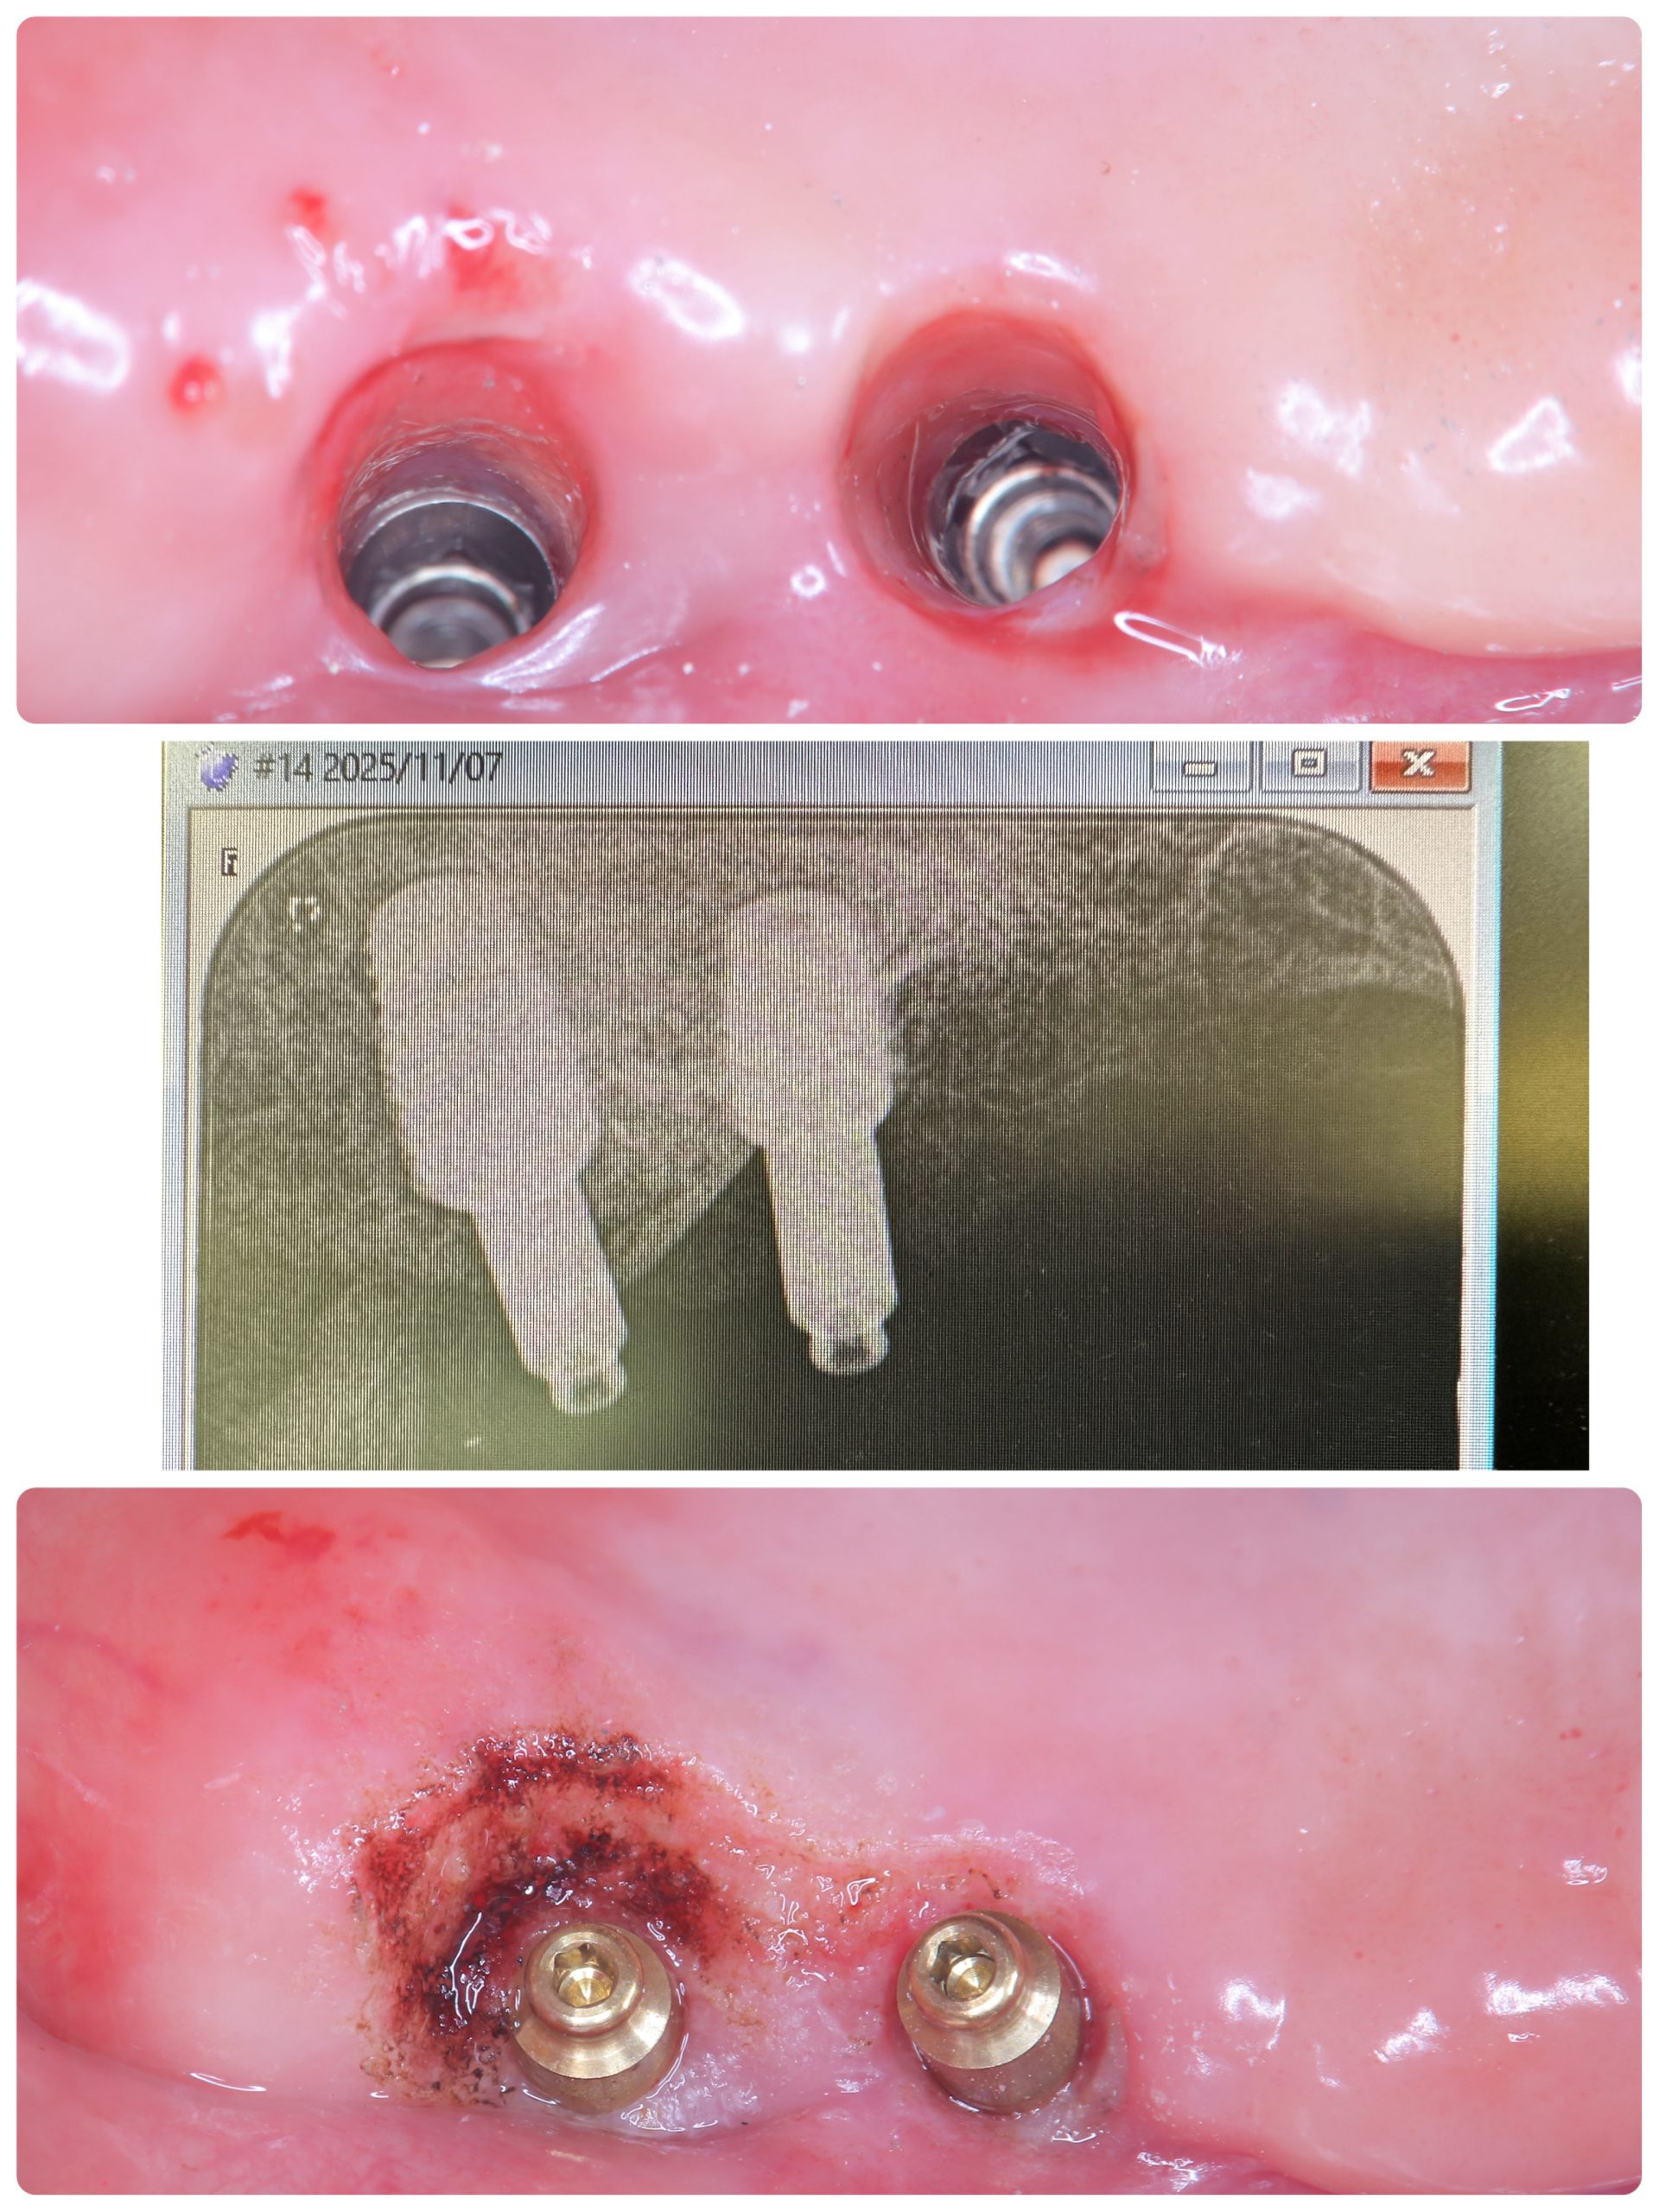

朝イチより、ケラター印象I.O.D

次のお方はオペ後6w、ISQも80台、仮歯まで

次のお方は、本年4月に抜歯即時、ソケットシールド

セミルーナフラップした方の頬側の骨再生画像確認

ソケットシールドしてるから、吸収なくボリーュミー